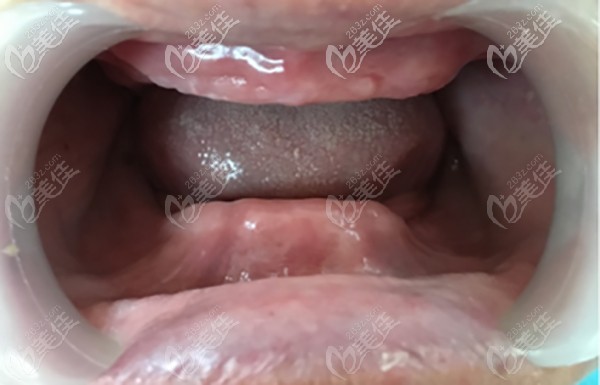

杭州美奧口腔醫(yī)院是經(jīng)相關(guān)部門批準(zhǔn)成立的正規(guī)的私立口腔連鎖機構(gòu),也是一所高端先進的美式口腔機構(gòu),擁有近2000平米的使用面積,開設(shè)了牙齒種植、牙齒矯正、牙齒修復(fù)、牙齒美白、兒童齒科及口腔疾病治療6大特色齒科診療,不斷的引進新的技術(shù),壯大醫(yī)生團隊,自成立至今,美奧口腔在杭州當(dāng)?shù)氐目诒际窍喈?dāng)不錯的。 美奧口腔目前在核心城市,如長沙、常德、、蘇州、烏魯木齊、杭州、天津、合肥、南京、無錫等地開設(shè)詳細(xì)>